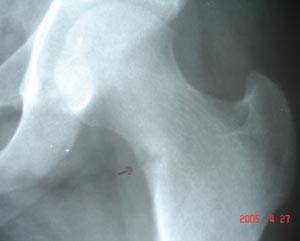

Hairline cortical fracture

It shows the bony trabeculae are interrupted across the fracture site. It may show step in the cortex.